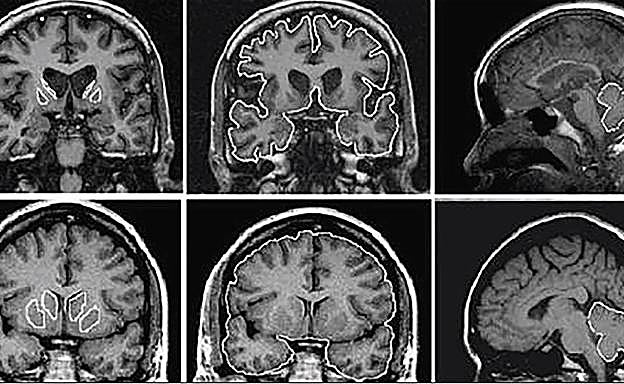

Imágenes de un cerebro afectado por la enfermedad de Huntington (arriba) y abajo, un cerebro sano. R.C.